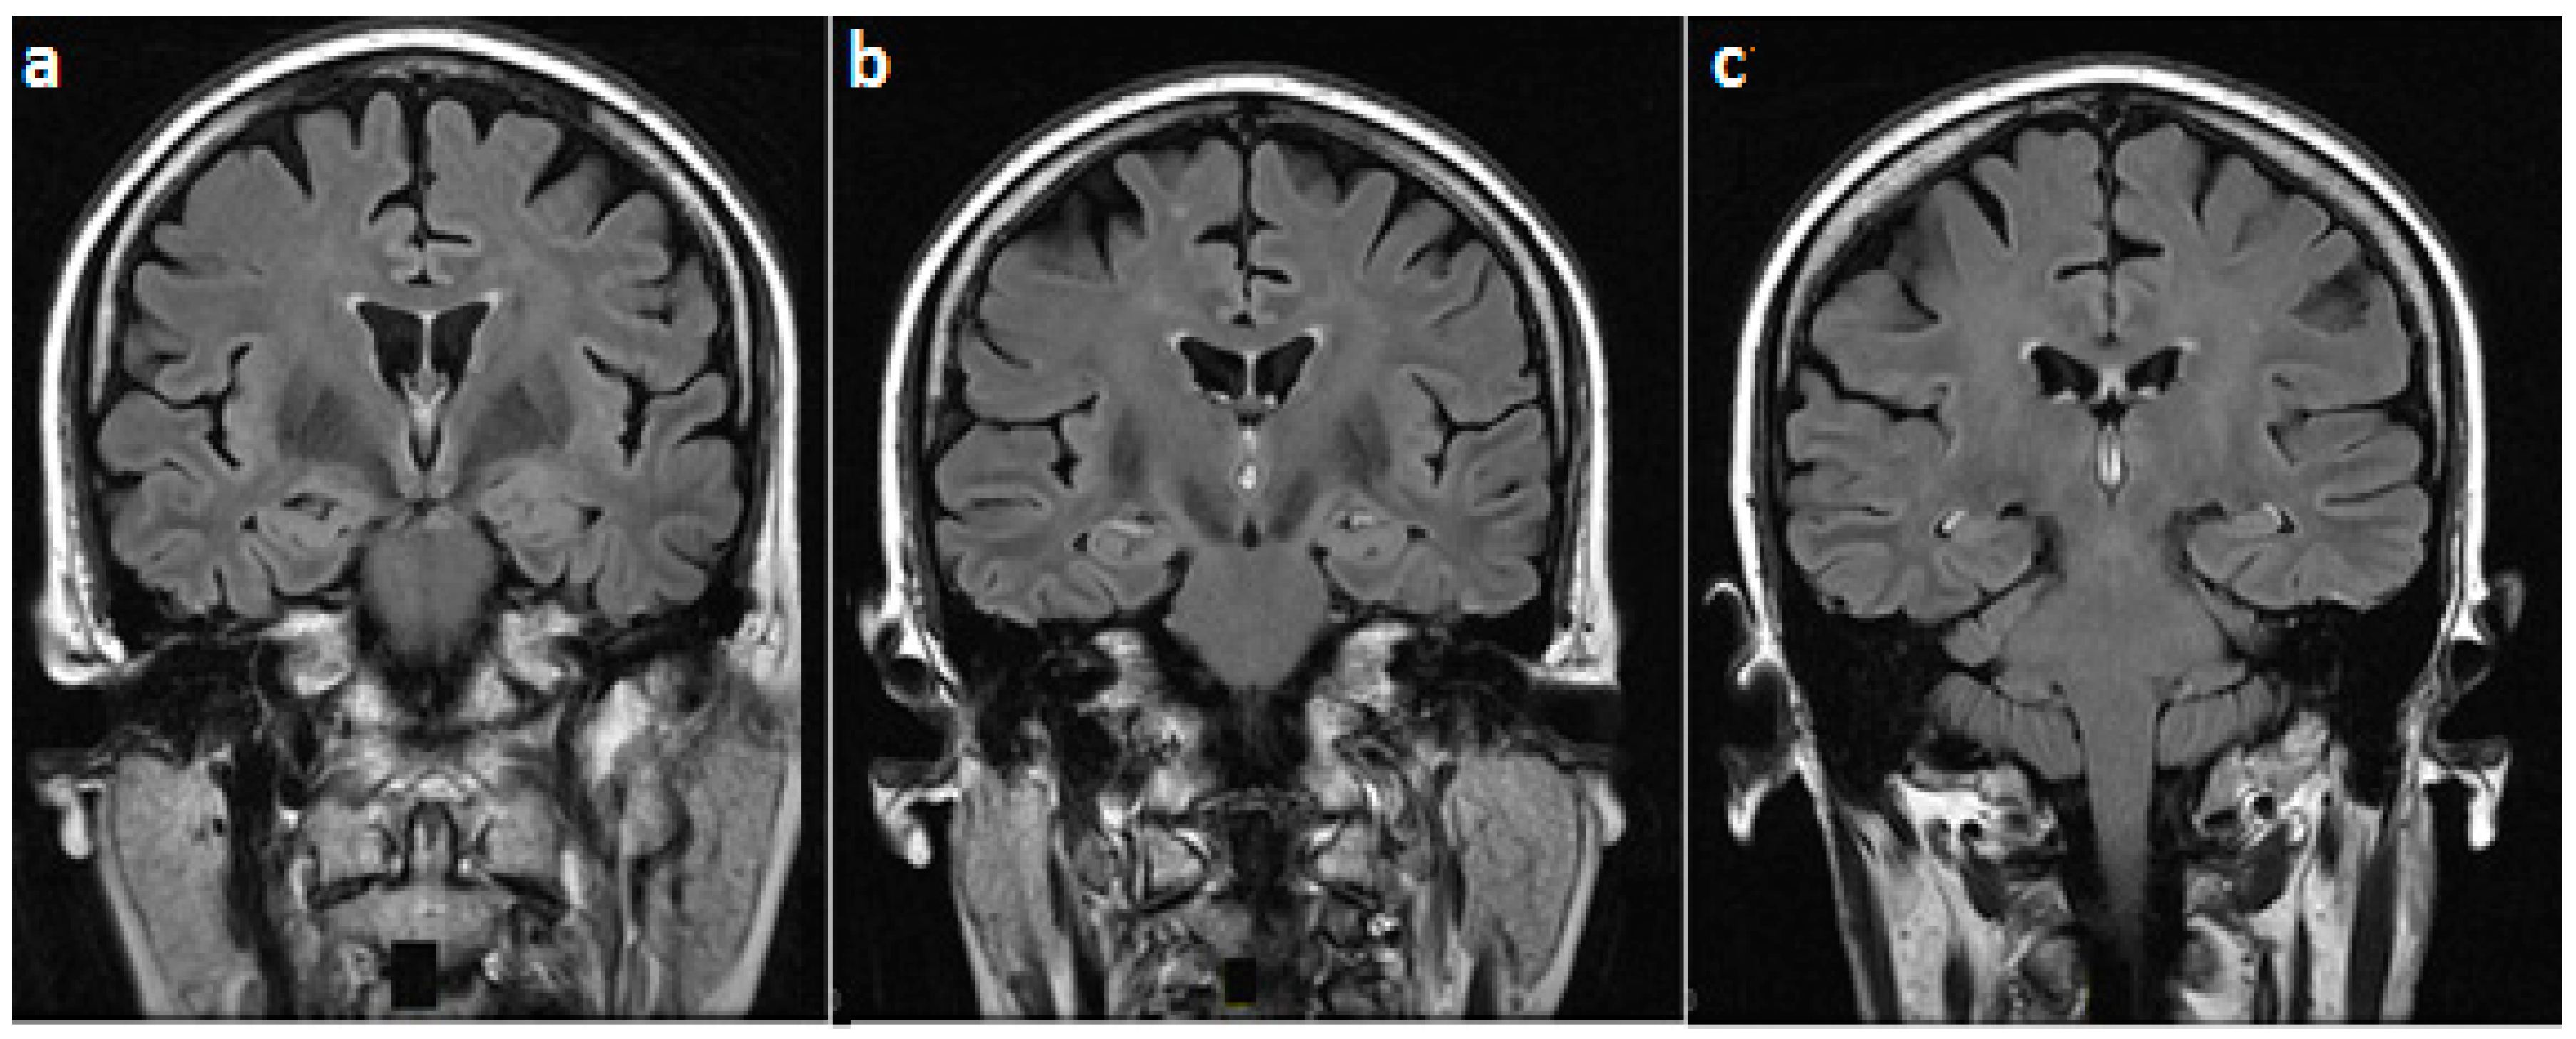

Isolated Mammillary Bodies Damage—An Atypical Presentation of Wernicke Syndrome

2. Case Presentation